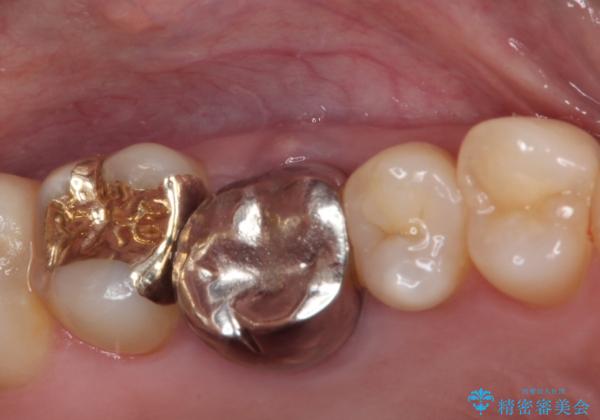

上顎奥歯で目立たないことから、ゴールドインレー(PGAインレー)による修復治療をおこなうこととしました。

ゴールドインレーは銀歯のインレーやセラミックインレーと比べ、「技工操作の精度が高く、適合が著しく良い」というメリットがあります。特に上の奥歯は歯科医師の操作が行いにくいため、「適合の良さ」は再治療のリスクを防ぐ上でとても重要な要素となります。

上の奥歯は金属色が見えることもないため、審美的な問題は全くありません。

咬み心地はとても良好で、全く違和感がなく、患者様には大変満足していただきました。